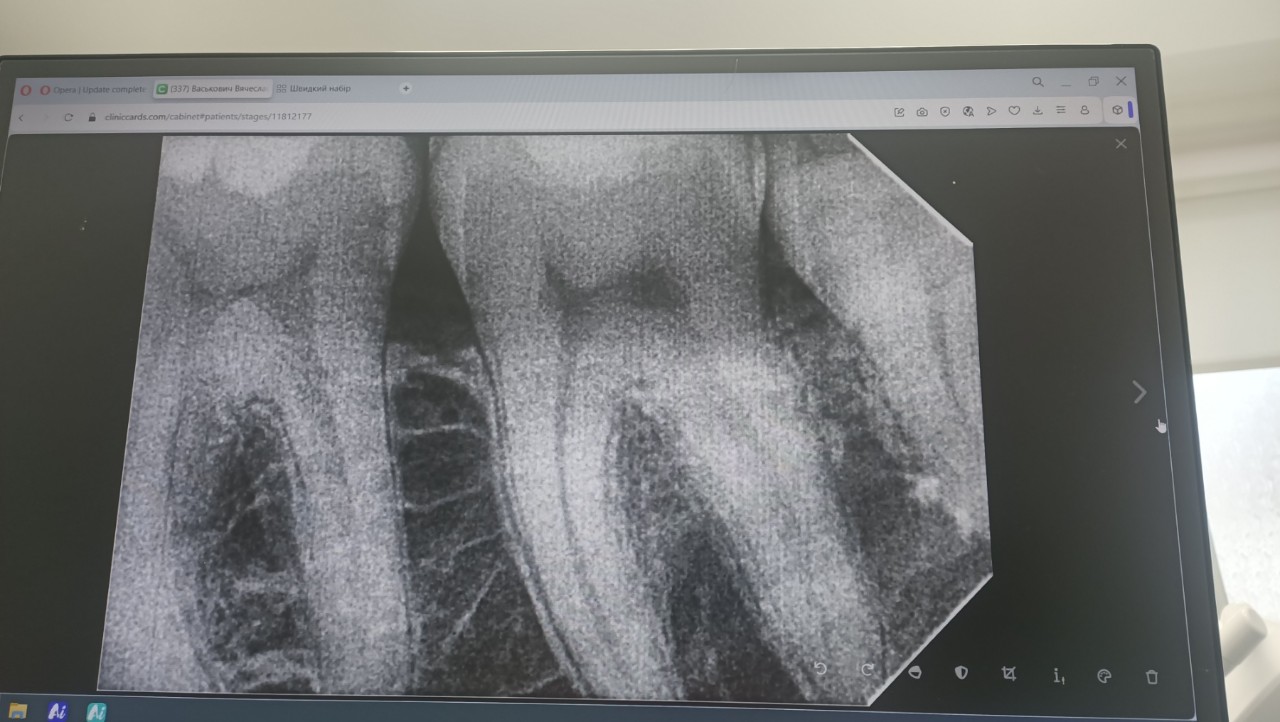

Сделал недавно снимки 6 и 7 зубов (пломбированные), прилагаю.